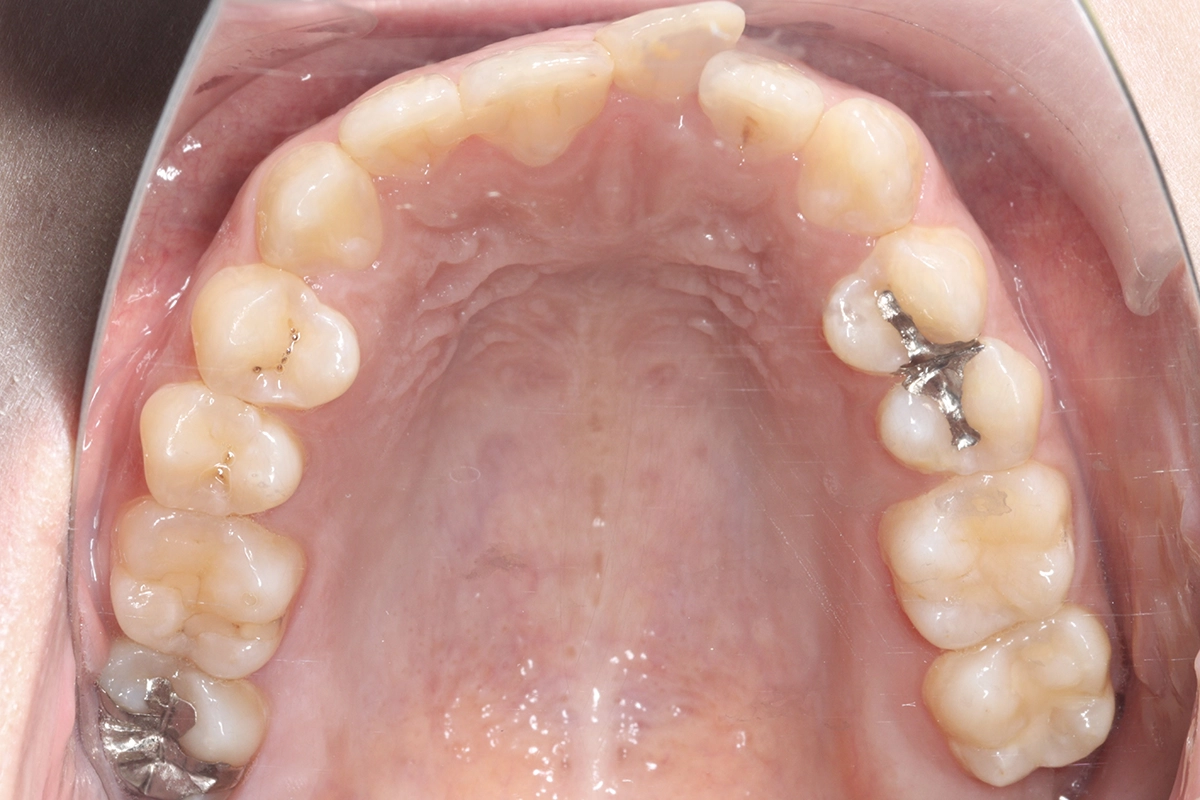

上顎

before

叢生(ガタつき)

上の前歯のうち1本が前方に飛び出し、隣の歯と重なり合っている状態です。歯ブラシが届きにくく、虫歯や歯周病のリスクが高まります。

前方に飛び出していた歯が歯列の中に収まり、滑らかなアーチを描くようになりました。